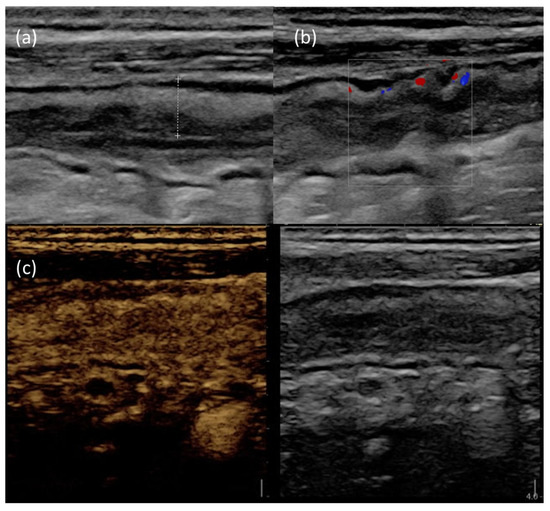

Figure 3 provides an example of IUS images showing ultrasonographic parameters of disease activity.

Figure 3.

IUS images of the terminal ileum in a patient with active CD. (a) B-mode IUS showing increased BWT (dotted line) with preserved wall stratification. (b) The use of color doppler highlights increased intramural vascularization. (c) After Sonovue® injection, the affected bowel wall shows increased contrast enhancement.